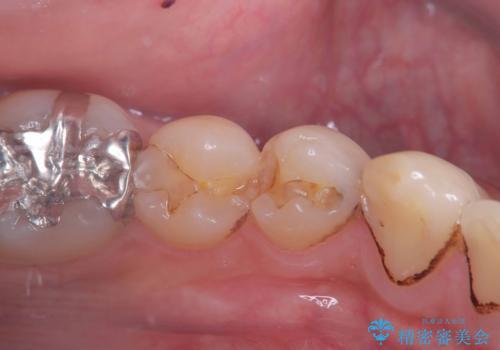

- 治療計画

- 1つ目の医院にて虫歯の治療を行い詰め物を入れたがその後、痛みを感じるようになった。2つ目の医院を受診したところ根の先に膿があるため、根の治療が必要と言われた。そこで根の治療を2回程度受けたが、毎回15分くらいで治療が終わり、痛みもとれず不安を感じたため当院に来院された患者様です。